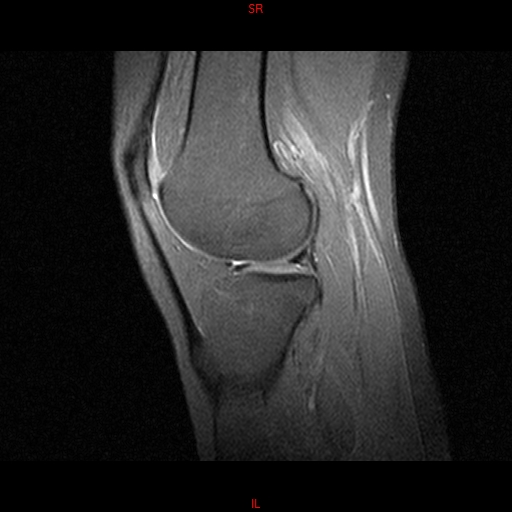

• Resonancia PATOLÓGICA MENISCOPATIA INTERNA DP SAGITAL

• Resonancia NORMAL RODILLA SAG DENSIDAD PROTONICA

• Resonancia NORMAL RODILLA SAG T1